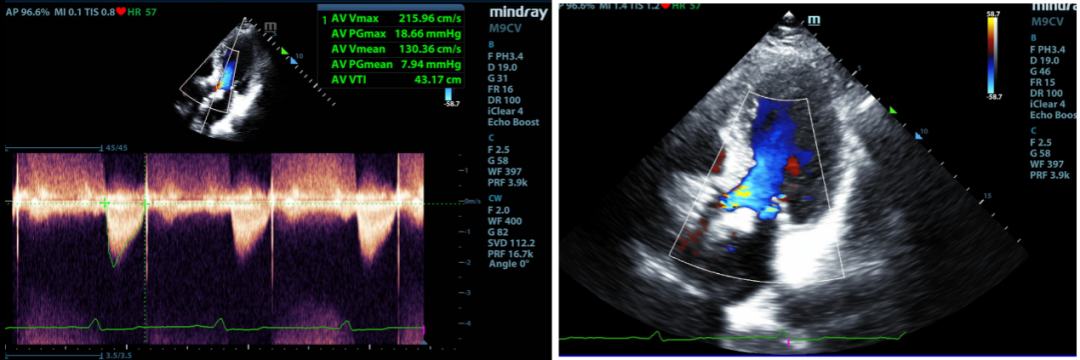

本次患者完成术后一年随访,心脏彩超提示:人工瓣支架位置固定良好,短轴塑性良好,支架扩张形态均匀一致,瓣叶启闭运动尚可,闭合欠佳;EF为55%,最大峰值血流速为2.15m/s,平均跨瓣压差为8mmHg,瓣口面积约为1.9cm²,瓣环内未见明显反流,瓣架前后缘探及少量瓣周漏。